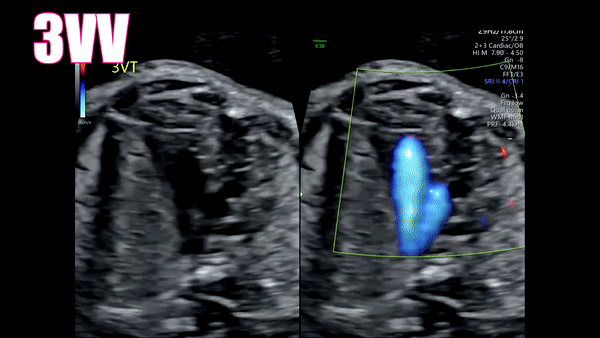

5th: 3VV

As you move out of your 4CH view caudally and into the outflow tracts the next part of the fetal heart should be the 3 vessel view (3VV). The 3VV consists of the Pulmonary, Aorta, and Superior Vena Cava (SVC). Think P-A-S. They should be properly sized. The Pulmonary should always be your larger vessel. The Aorta should be in the middle and mid sized. Your SVC should be the smallest of the 3 arteries. Remember PAS for quick reference.

6th: 3VT

As you continue moving caudally the 3VV will naturally turn into the 3 vessel trachea view (3VT). The 3VV turns into the 3VT when the Ductus arteriosus portion of the Pulmonary artery and the Aorta merge together. When this merge happens a “V” shape is created. This is located to the left of the trachea. I sometimes find it easier to use my color Doppler in this setting as the Pulmonary and Aorta should be going the same direction so they should be the same color.